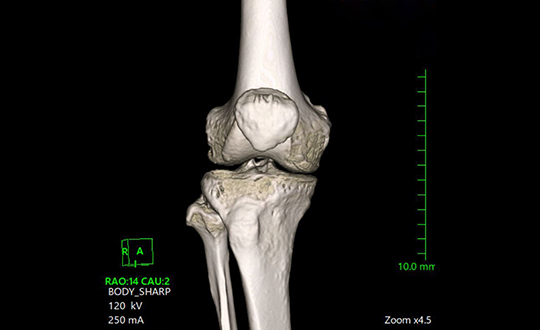

人工膝関節置換術は、すり減って痛みの原因となっている膝関節の表面(主に大腿骨・脛骨、必要により膝蓋骨)を整え、金属や樹脂(ポリエチレン)の人工関節に置き換える手術です。変形や炎症で生じる強い痛みを軽減し、歩行や日常生活動作を改善することを目的とします。